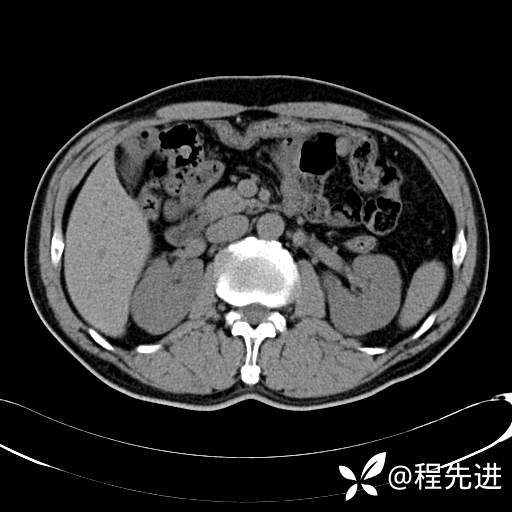

患者性别:男

患者年龄:65岁

简要病史:腰痛2月,体检发现左肾占位5天

排泄期:

肾透明细胞癌 (27)